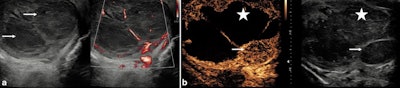

Scrotal trauma. After a 45-year-old man underwent sperm retrieval from the left testis for management of infertility, he presented with continuing pain following the procedure. The B-mode ultrasound (a) demonstrated a serpiginous low reflective area in the mid aspect of the testis (arrow). On the color Doppler examination (b), some shunting of blood (arrow) was visible to the lateral aspect of the low reflective area. On the contrast-enhanced ultrasound examination (c), the shunt was again noted (arrow) and the area of hematoma formation was visible (star). All figures courtesy of Dr. Faiz Jabbar, Dr. Dean Huang, and Prof. Paul Sidhu and presented at ECR 2025.

Infarcted tumor -- pure seminoma. A 41-year-old man with a 48 x 30 mm right testicular mass, which was an avascular infarcted tumor with multiple small vascular satellite lesions. The lesions were of low reflectivity (arrows) and did not demonstrate increased flow on microvascular imaging (a). On contrast-enhanced ultrasound (b), the large lesion was avascular (star) and the smaller inferior lesion (arrow) had abnormal enhancement, with increased early arterial enhancement and subsequent rapid washout in keeping with a germ cell tumor. On histology, this was found to be a pure seminoma.